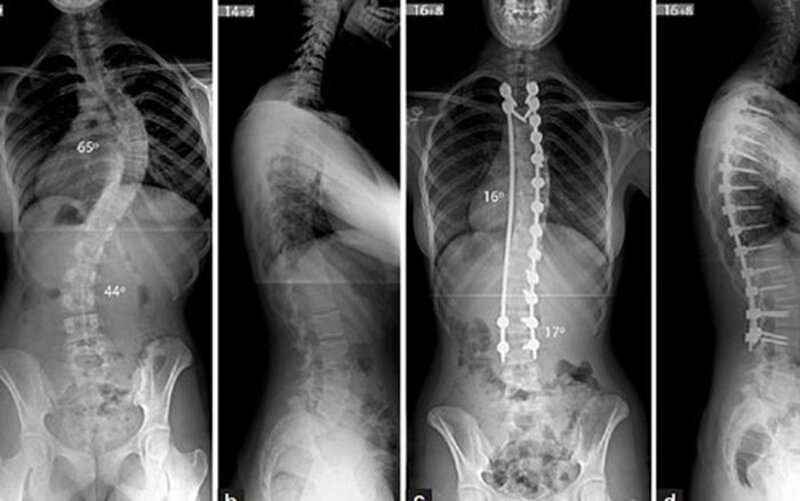

2.1 Chụp X quang

Chụp X quang là phương pháp có thể thấy được dấu hiệu đang lây lan của ung thư vào xương. Đây là được xem là loại xét nghiệm đơn giản và thường được sử dụng đầu tiên khi bệnh nhân có những triệu chứng đau xương. Đồng thời chụp X quang cũng giúp phát hiện tình trạng gãy xương do ung thư di căn.